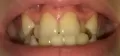

Вот фото зубов:

Возможно ли исправить винирами, и какими? Спасибо!